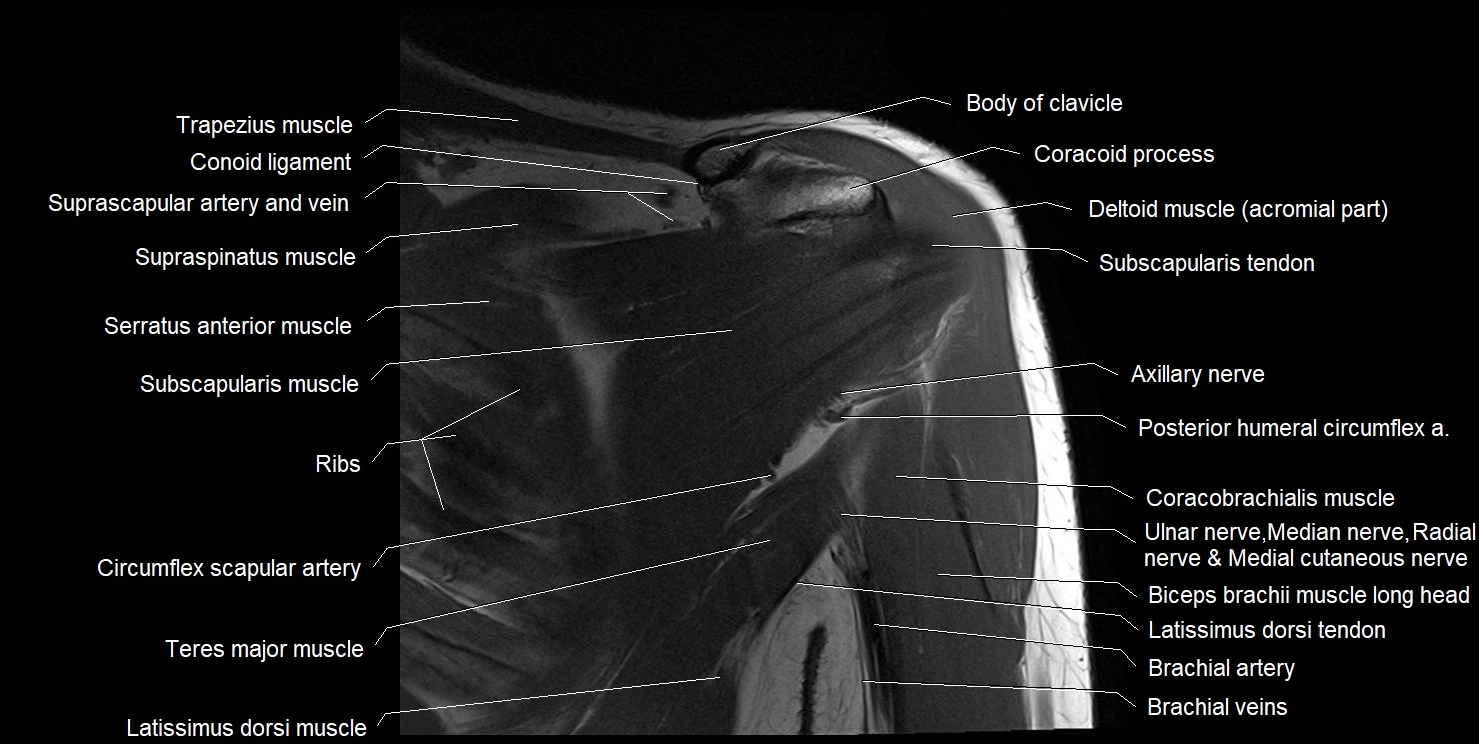

MRI images

image